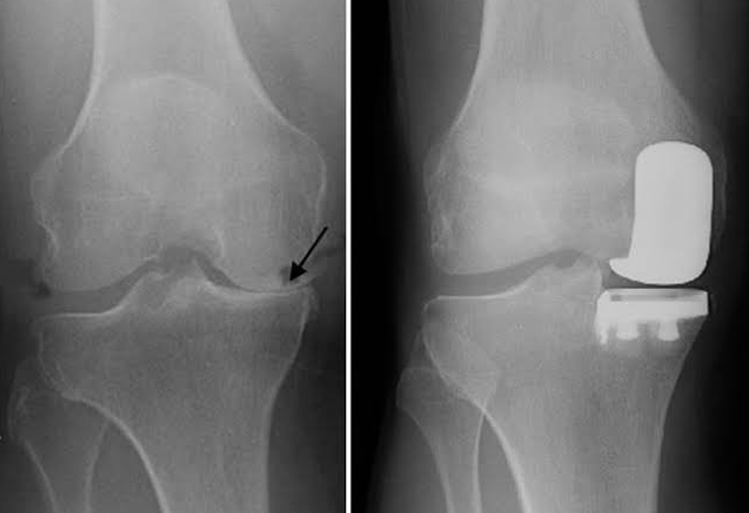

Unicompartmental (Partial) Knee Replacement

Advanced osteoarthritis that is limited to a single compartment may be treated with a unicompartmental knee replacement. During this procedure, the damaged compartment is replaced with metal and plastic. The healthy cartilage and bone, as well as all of the ligaments, are preserved.

Partial Knee Replacement